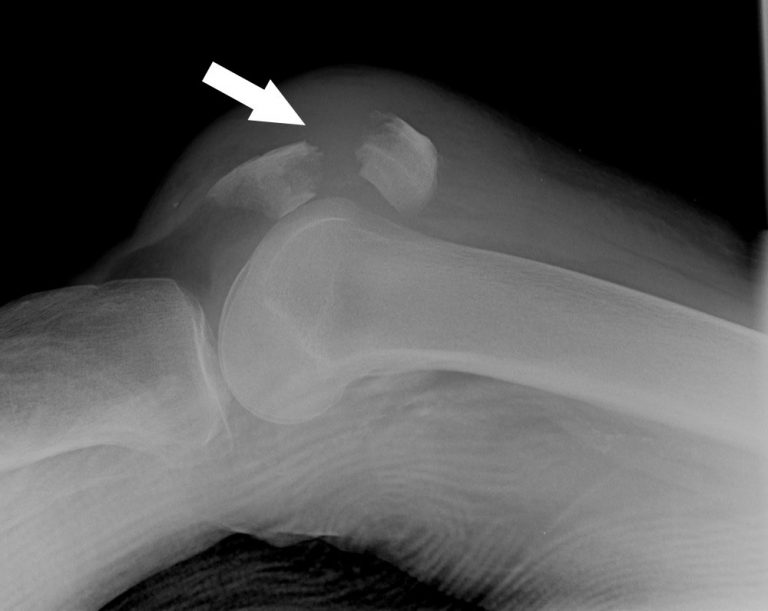

from westjem.com

— chirurgie ?    — la fracture du genou concerne le plateau tibial (extrémité supérieure du tibia), le fémur distal (extrémité inférieure.  la rotule agit comme un bouclier pour l’articulation du genou. Le traitement d'une fracture du genou dépend de sa gravité : Lors de ce type de traumatisme, l’articulation saigne de l’intérieur, ce qui provoque dans tous les cas un gonflement à l’avant de l’articulation.    — les fractures de la rotule peuvent entraîner divers symptômes, tels que : Une douleur intense au niveau du.  la fracture de rotule intervient la plupart du temps suite à une chute de sa hauteur avec pour conséquence un choc direct sur l’avant du genou.    — vous avez une fracture de la rotule ? Découvrez son traitement, sa rééducation, le temps de guérison et.

A Rare Knee Fracture with Underestimated Severity The Western Journal of Emergency Medicine